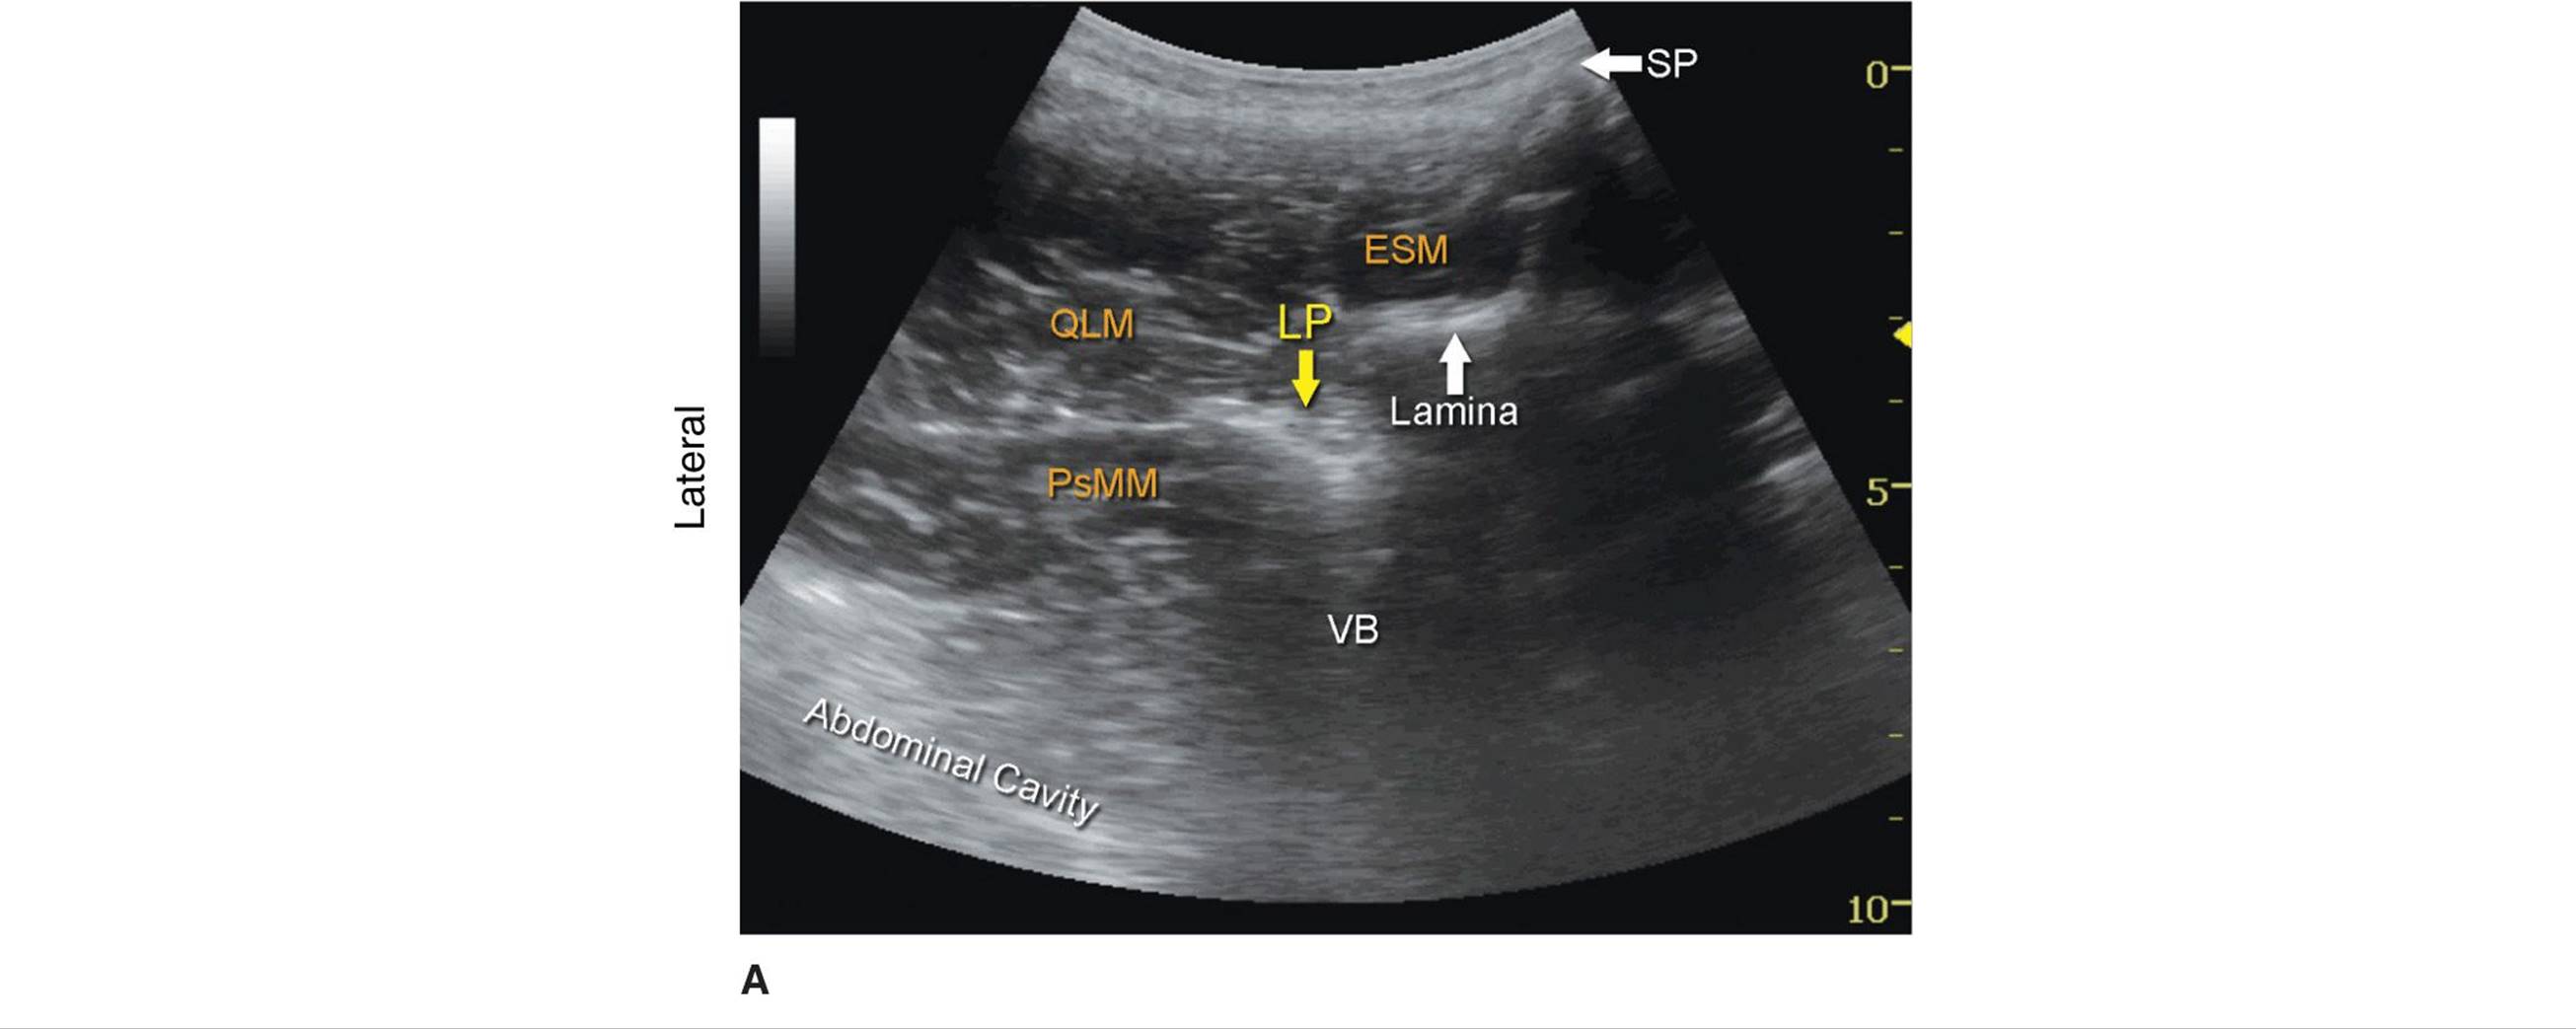

Kirchmair and colleagues were among the first to describe the sonoanatomy of relevance for LPB.3 They reported the ability to accurately guide a needle to the posterior part of the psoas muscle, where the roots of the lumbar plexus are located, using ultrasound guidance in cadavers.4,5 Since, significant advances in ultrasound technology have taken place, allowing for much improved image quality, which have allowed Karmakar and colleagues to devise an alternative approach to the lumbar plexus using ultrasonographic identification of the transverse processes as the guide.6 With this scanning technique, the transducer is positioned 4 to 5 cm lateral to the lumbar spinous process at the L3-L4 level and directed slightly medially to assume a transverse oblique orientation (Figure 46-4). This approach allows imaging of the lumbar paravertebral region with the erector spinae muscle, transverse process, the psoas major muscle, quadrates lumborum, and the anterolateral surface of the vertebral body (Figure 46-5A, B, and C). In the transverse oblique view, the inferior vena cava (IVC), on the right-sided scan, or the aorta, on the left-sided scan, also can be seen and provide additional information on the location of the psoas muscle, which is positioned superficial to these vessels. In this view, the psoas muscle appears slightly hypoechoic with multiple hyperechogenic striations within. The lower pole of the kidney can often be seen, when scanning at the L2-L4 level, as an oval structure that ascends and descends with respirations (Figure 46-6). The key to obtaining adequate images of the psoas muscle and lumbar plexus with the transverse oblique scan is to insonate between two adjacent transverse processes. This scanning method avoids acoustic shadow of the transverse processes, which obscures the underlying psoas muscle and the intervertebral foramen (angle between the transverse process and vertebral body) and allows visualization of the articular process of the facet joint (APFJ) as well. Because the intervertebral foramen is located at the angle between the APFJ and vertebral body, lumbar nerve roots often can be depicted.

FIGURE 46-5. (A) Ultrasound anatomy of the lumbar paravertebral space using transverse oblique view. SP, spinal process; ESM, erectors spinae muscle; QLM, quadratus lumborum muscle; PsMM, psoas major muscle; VB, vertebral body. The lumbar plexus root is seen just below the lamina as it exits the interlaminar space and enters into the posterior medial aspect of the PsMM. (B) Needle path in ultrasound-guided lumbar plexus block using transverse oblique view. LP, lumbar plexus; PsMM, psoas major muscle; VB, vertebral body. (C) Spread of the local anesthetic solution with lumbar plexus block injection. Due to the deep location of the plexus, spread of the local anesthetic may not always be well seen. Color Doppler imaging can be used to help determine the location of the injectate.